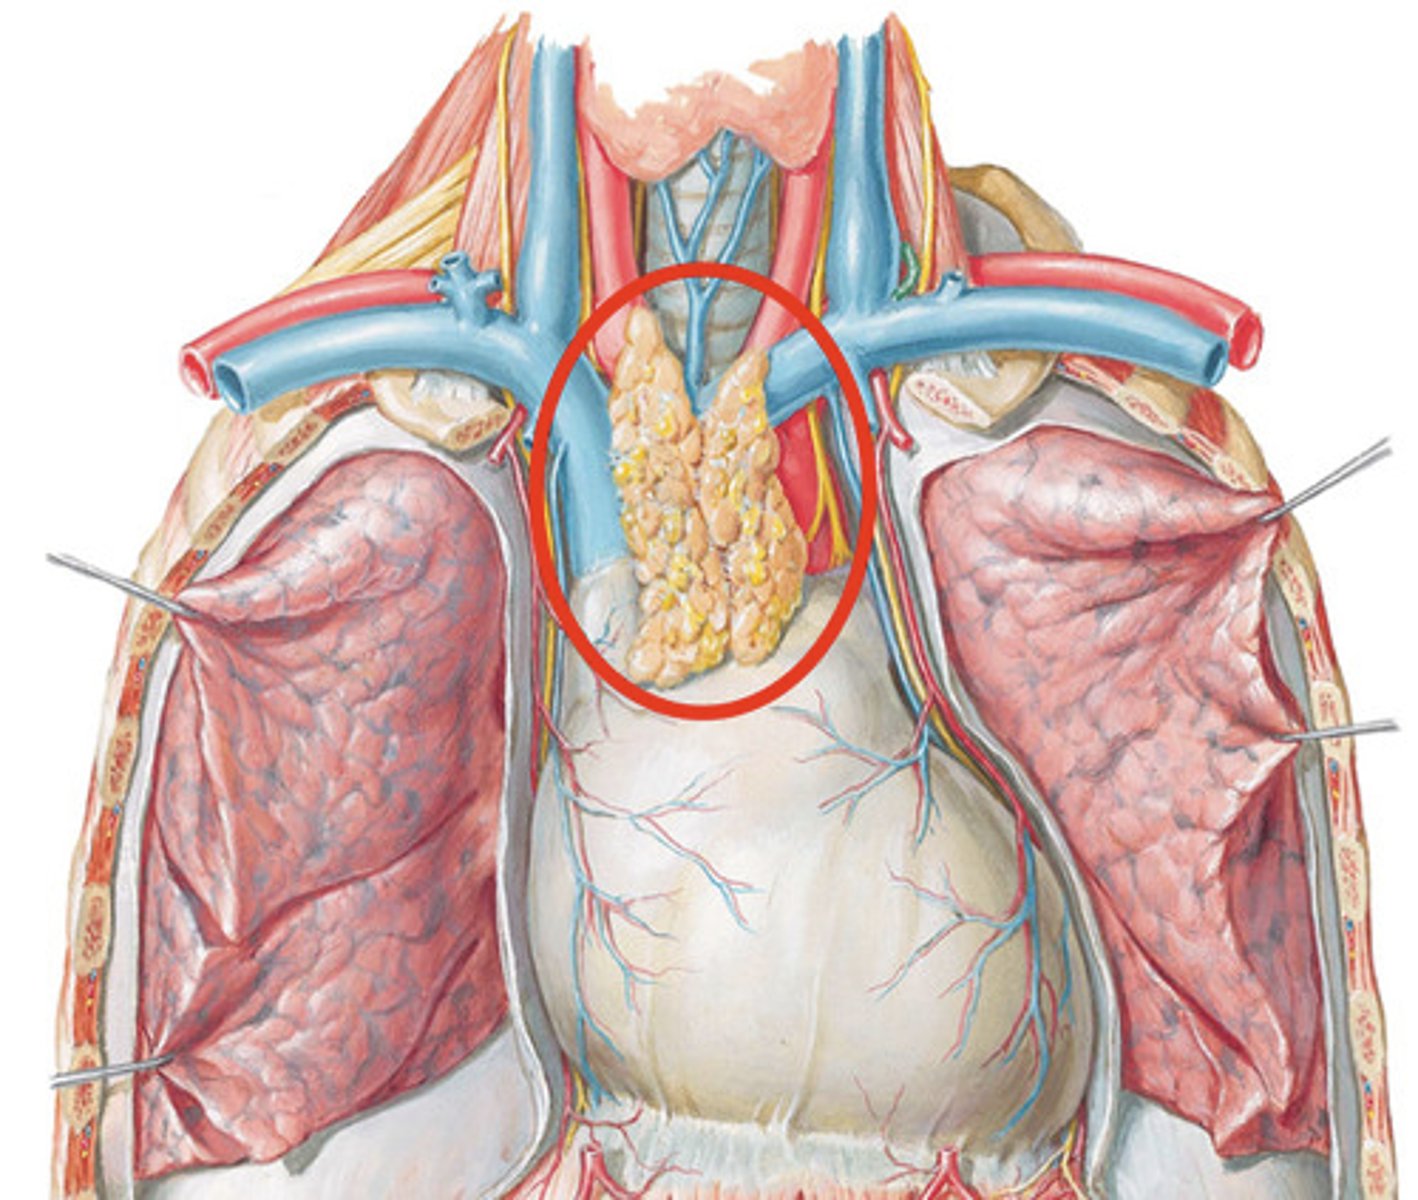

T cells

A type of lymphocyte that is created in the thymus; produce substances that attack infected cells in the body

What does the thymus do?

Site of T cell differentiation and maturation

<p>Site of T cell differentiation and maturation</p>